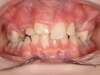

Avant

Après